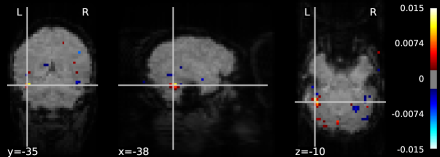

Two of the parameters are fixed: the regularization and the relaxation , which is set to 0.6 for VAMP and to 0.95 for PRS. In this setting, VAMP achieves smaller values of the objective faster than all other methods and for all the three classes considered, as shown in Figure 4. The weight map obtained in “face” classification is displayed in Figure 3.

In Figure 3 (right), we study how the performance of our scheme changes in this experiment as a function of . We can see the performance does not change considerably as long as is set small enough. While this has been often observed by us, further experiments must be performed to ensure such behavior is indeed recurrent. If that is the case, it should be straightforward to devise an adaptive scheme for .